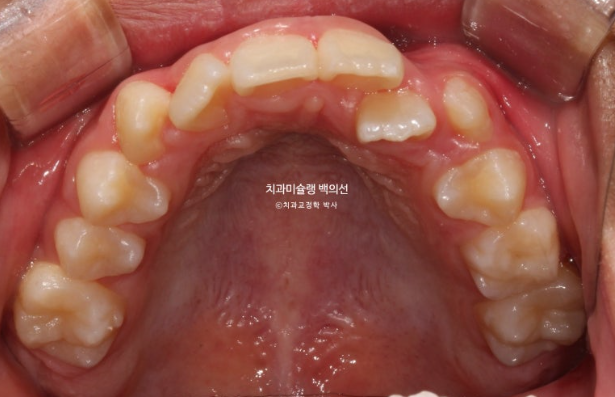

그 사이 하나 남아있던 유치가 빠지고 완전한 영구치열에 접어들었습니다.

24.09

중심선 개선을 위해 추가장치 제작을 하기로 합니다.